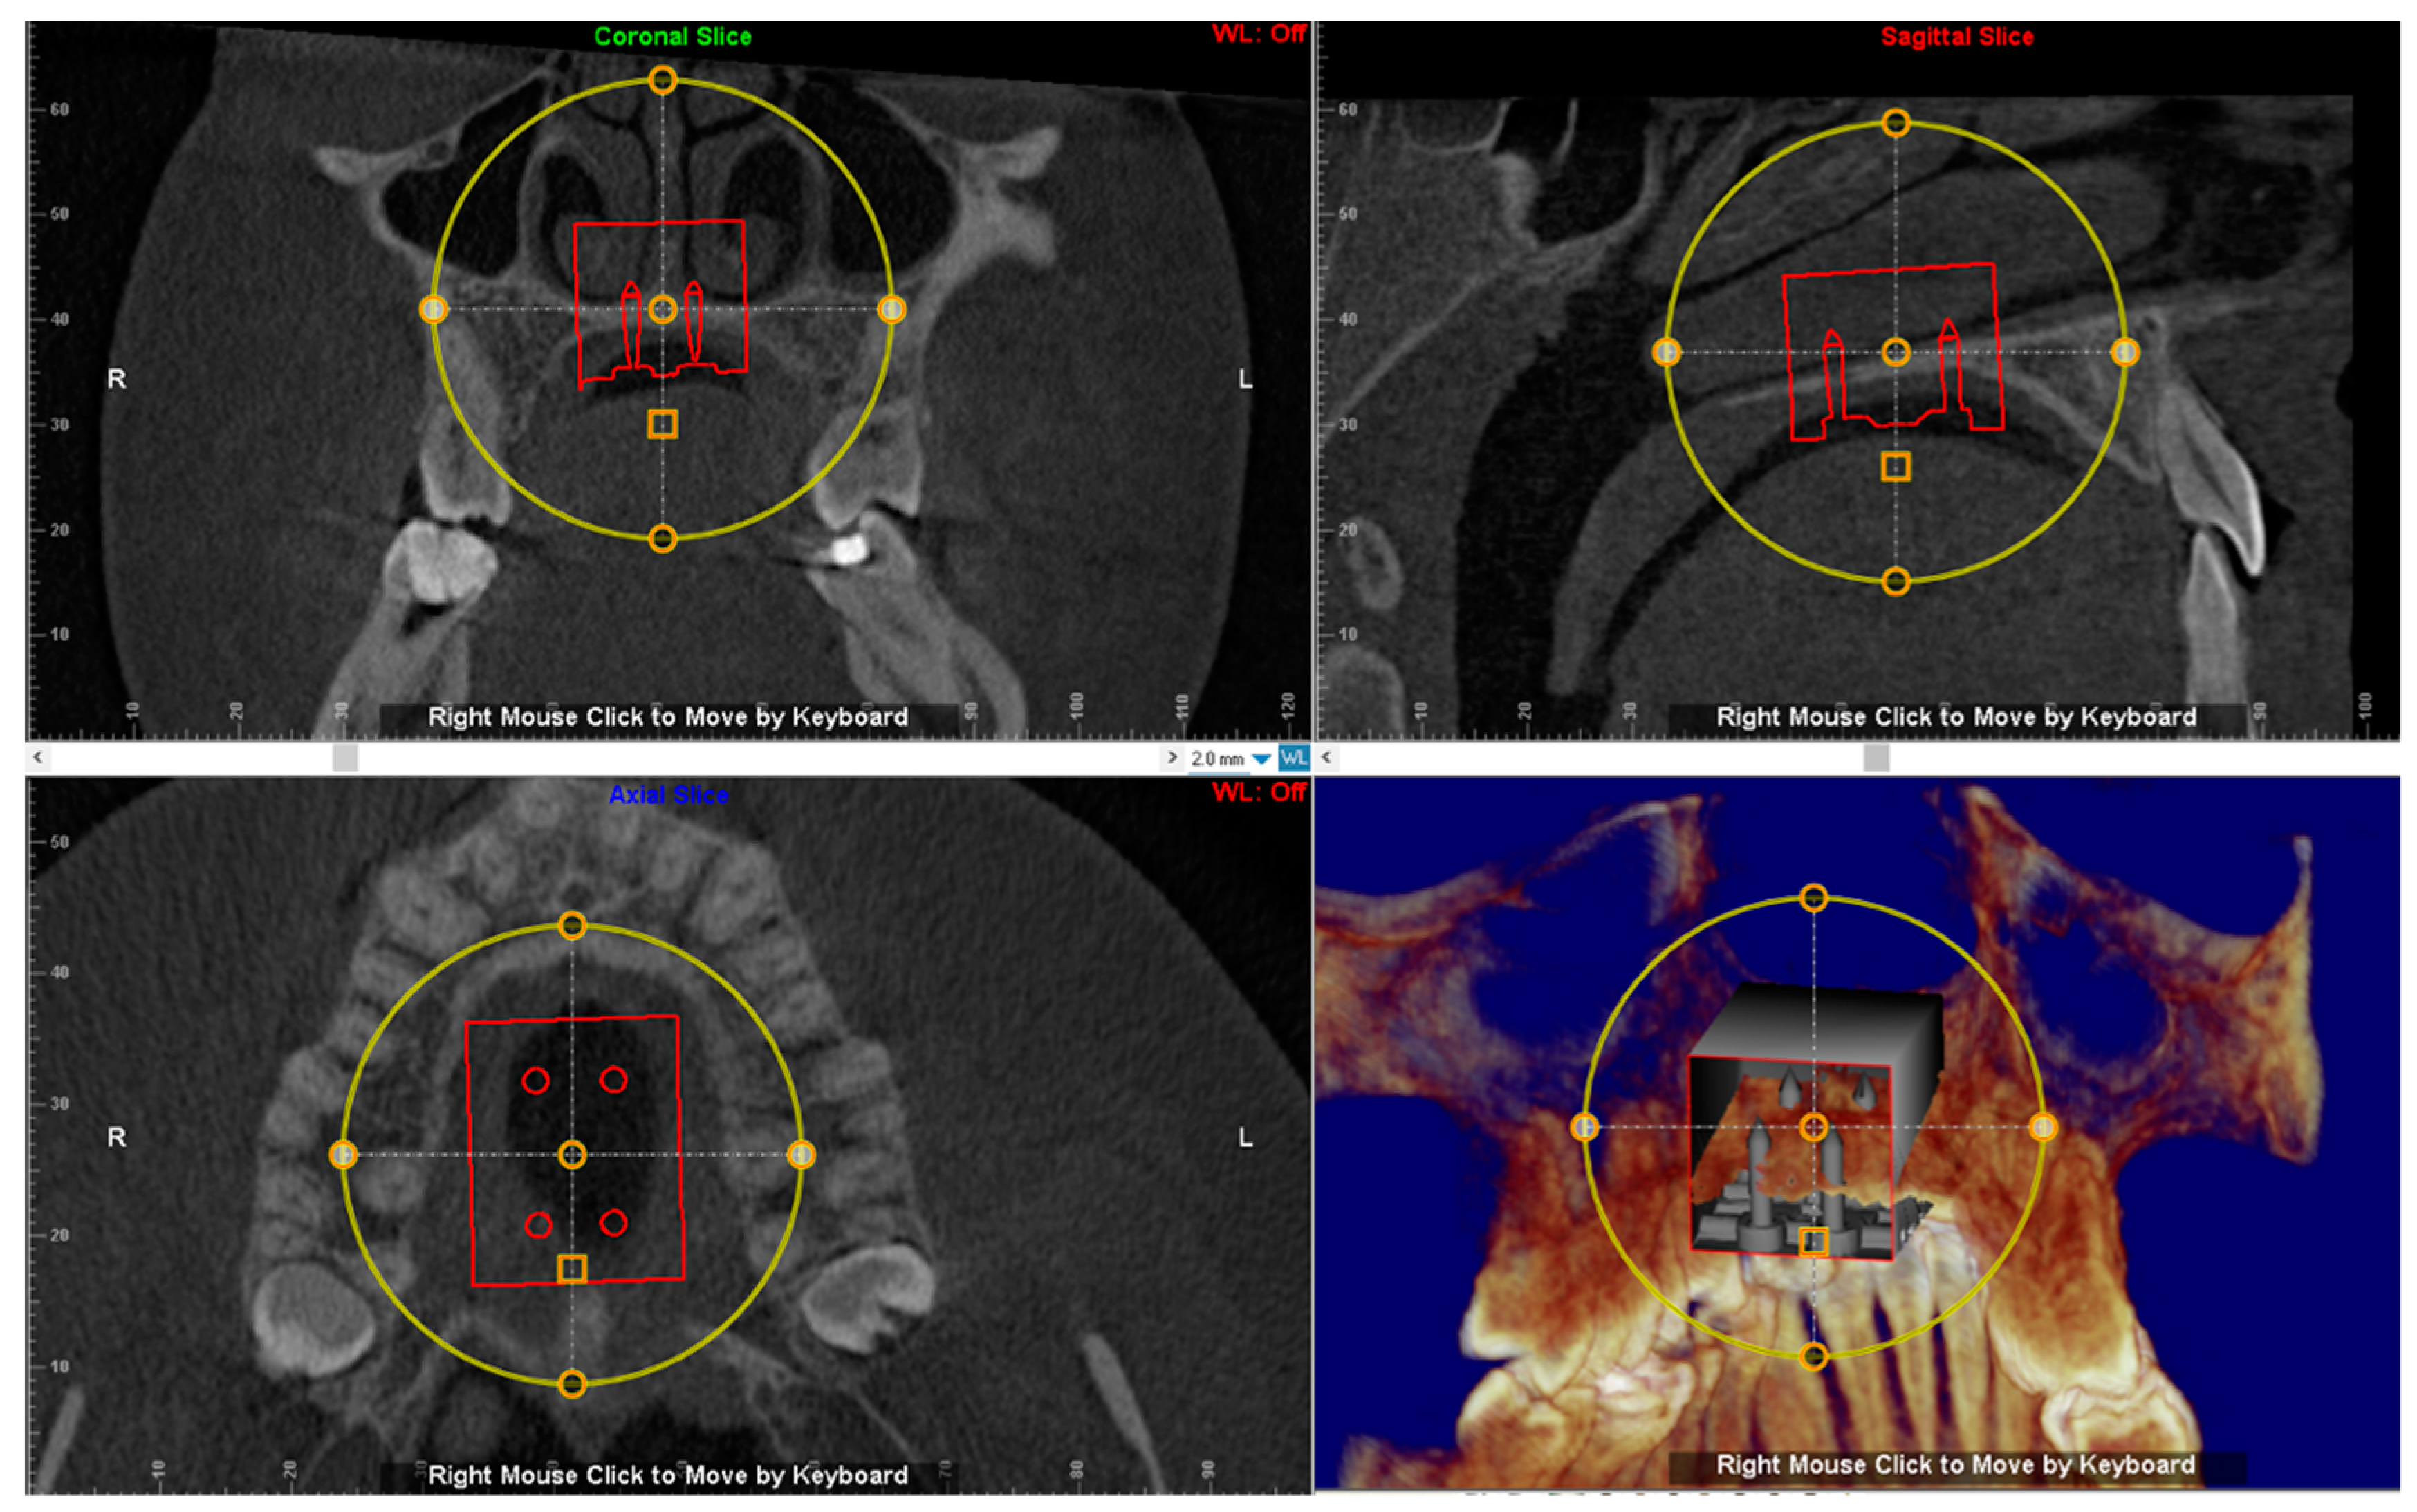

2.3. CBCT Examination

3.2. Digital Workflow for Planning MSE Device